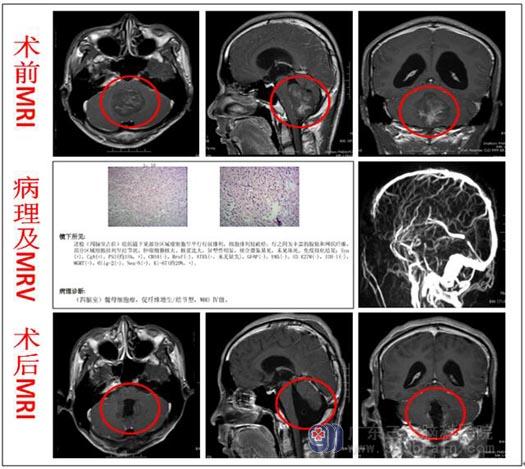

入院后检查头颅MRI显示:1.四脑室--小脑蚓部区域占位性病变并幕上梗阻性脑积水,大小约44mm×43mm×49mm,肿瘤性质、分类待定; 2.部分空泡蝶鞍;3.右侧上颌窦粘膜下囊肿;4.脑MRV:上矢状窦、直窦及左侧横窦局部变细,考虑发育与血流因素。

排除手术禁忌症后,由鲁明副院长主刀,在全麻下行“四脑室巨大占位性病变切除术”,术中见肿瘤质脆、硬混杂,边界相对尚清,与周围粘连紧密,小脑被压向两侧,向下挤压脑干,瘤内有卒中,血供中等,显微镜下予以分块全切除肿瘤,手术顺利。术后病理:髓母细胞瘤,WHO IV级。